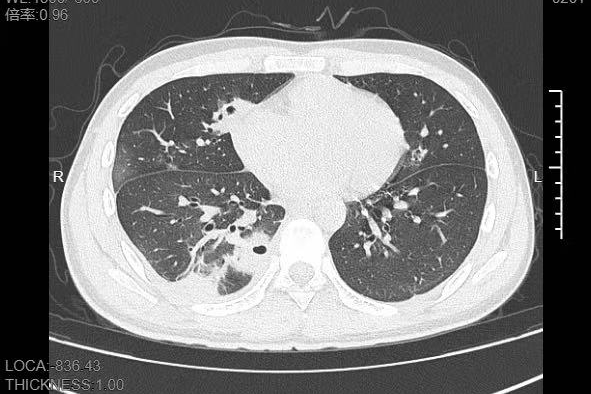

更难受的是右下胸部传来的疼痛,像有根针在扎,深呼吸、咳嗽时更是疼得直冒冷汗。熬到第三天,小林已经烧到39℃,赶紧来到宁波大学附属第一医院就诊。接诊的呼吸与危重症医学科丁群力主任医师一看他的症状,立刻安排了CT检查,结果显示:小林的肺里有十几个空洞,部分肺组织已经坏死,这是典型的血源性肺脓肿。

进一步的细菌培养和基因检测揭开了真相,小林的血液里检出了金黄色葡萄球菌,这种细菌,就藏在每个人的皮肤表面。医生介绍,“罪魁祸首就是那颗被挤掉的痘痘,这颗痘痘长在脸部‘危险三角区’,挤痘痘时的压力把细菌推进了血管,引发了败血症,接着细菌顺着血流跑到肺部,侵蚀肺组织。”